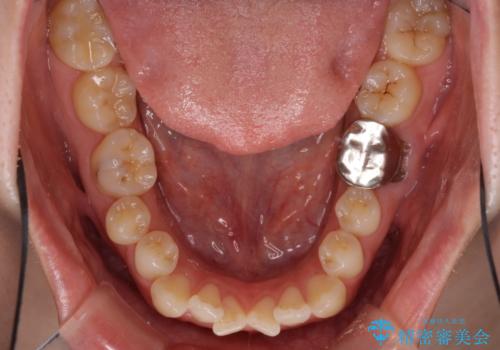

- 前歯のデコボコが気になるとのことで来院された患者様です。

目立たない装置と金属のワイヤーで矯正治療を行うこととしました。

奥の銀歯も気になっていたため、矯正治療後にセラミッククラウンにて補綴することとしました。